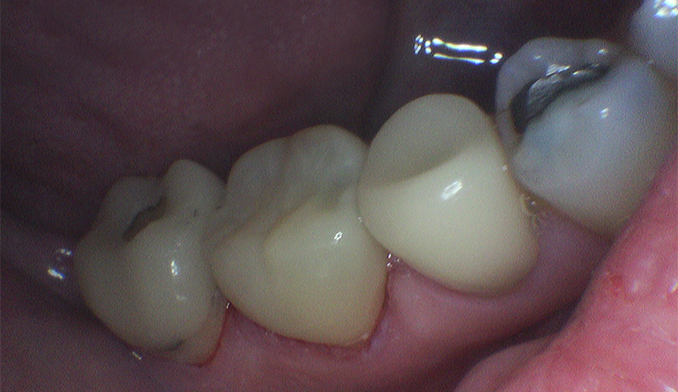

Same-Day Crown for Broken Molar

The patient broke a lower molar (second tooth from the back) while eating. Fortunately, the tooth was salvageable. We completed a same-day crown within two hours, restoring full strength and function.